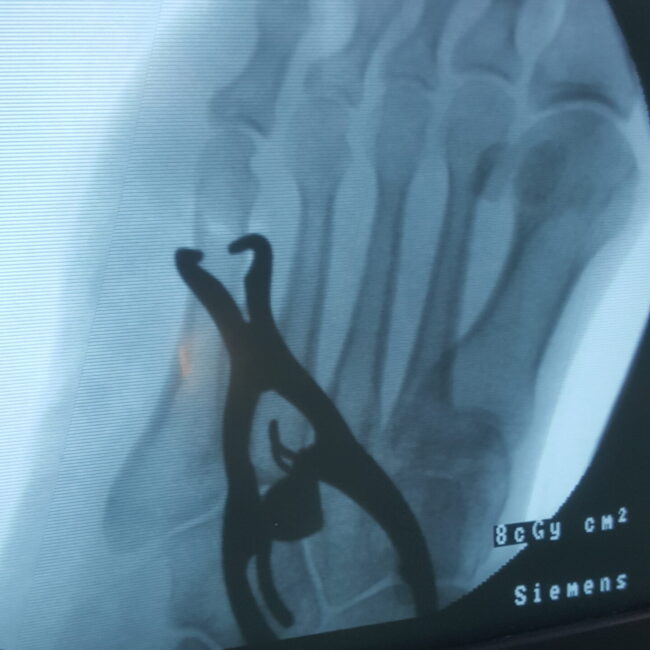

Percutaneous Pinning

This method involves thin wires or pins placed through the skin. It is used for wrist, hand, or finger fractures. Dr. Imran Salim Malik uses this to avoid large cuts and reduce healing time.